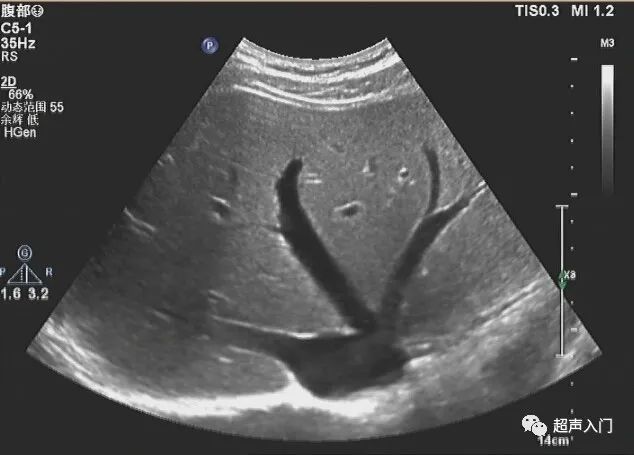

不急,朋友,你是否愿意从超声图像开始呢?比如,这像不像我们平时见到的肝?

图源:网络